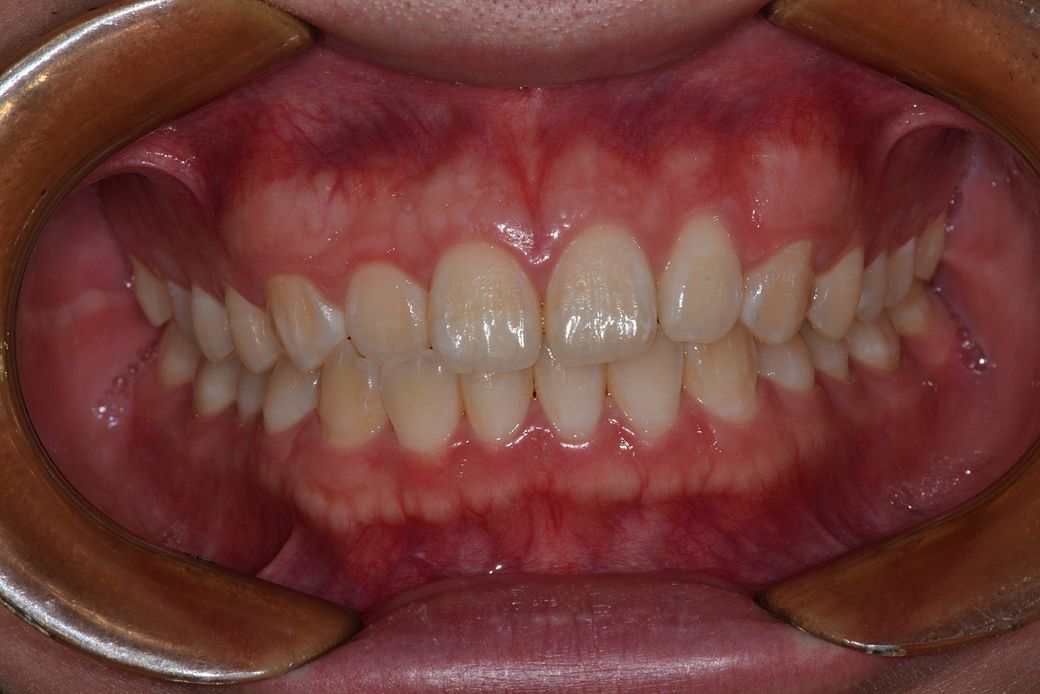

단순히 파노라마 사진만으로는 알 수 없으며 정확히 계측을 해봐야할 것으로 보입니다. 현재 물리는 정도로 불편감이 없다면 지금의 치열배열 상태는 교정에 대상은 아닙니다. 다만 환자분이 불편감을 느끼고 해당 부위에 대한 심미적인 요구가 있다면 할 수는 있습니다. 다만 어떤 교정을 하는 것이 효과적일지는 다각도적인 평가를 더 해보아야 하며 교정 치과 방문 후 상담이 필요합니다.

- 사진상으로 보면 크게 교정이 필요하실꺼 같진 않습니다. 만약 교정을 하게 되신다면 교정분석을 해봐야 전체 교정을 할지 부분교정을 할지 판단할수 있습니다.